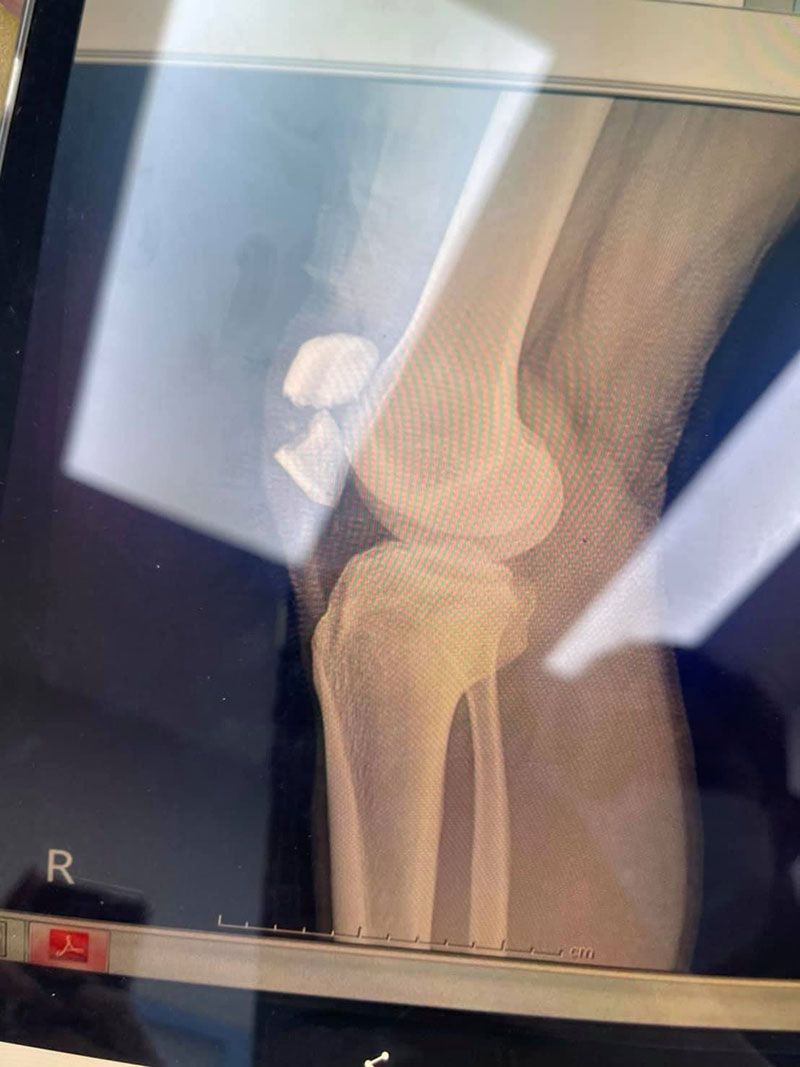

หนุ่มเล่นเซิร์ฟสเก็ตไร้อุปกรณ์ป้องกัน ล้มลูกสะบ้าแตกรักษากว่า 3 แสน พักฟื้น 6 เดือน

พี่มูลนิธิพาไปรพ. ใกล้สุดย่านลาดพร้าว (นี่เลยถามพี่เค้าปกติแล้วเราให้พาไปที่รพ. เราจะรักษาเลยได้มั้ย พี่เค้าว่าต้องไปที่ใกล้สุดก่อน) ถึงรพ. จัดการเอ็กซเรย์ หมอว่าไม่แค่หลุดละค่าาาา หนักกว่านั้น ต้องผ่าตัด พร้อมกับโชว์ศิลปะชิ้นเอกฟิล์มเอ็กซเรย์หัวเข่าให้ดู ก็ตามรูปเลยจ้า สะบ้าแตกแบบไม่เหลือเยื่อใยต่อกัน เลยคิดว่าจะย้ายรพ. ที่สะดวกละเป็นหมอกระดูกน่าจะดีกว่า เลยทำเรื้องจ่ายเงินและขอเอกสารส่งตัวไปอีกที่